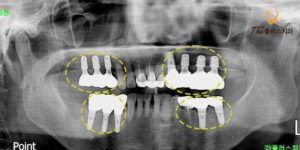

위 환자분은 60대 여성분으로,

하악 양쪽으로 어금니가 상실된 지 오래되었지만

앞쪽으로 식사가 가능하여 계속 미루다

앞니들 마저도 통증이 생겨

본 원에 내원해 주셨습니다.

육안으로 먼저 살펴 보았더니 환자분 말씀처럼

구치부가 다수 상실되어 있고

여러 치아도 흔들리고 있었으며,

특히 하악 어금니가 상악 어금니를

받쳐주지 못해 정출되어 있었습니다.

조금 더 정밀한 진단을 위해

파노라마 촬영을 진행해 보았더니

하악의 구치부는 빠진 지 오래되어

치조골이 잘 차올라 있었지만,

하악 소구치도 치주 질환으로 인해

치조골이 소실되어 치아가 흔들리고 있었습니다.

소구치 발치와 함께 구치부에

임플란트를 진행하기로 하였으며,

또한 반대쪽 소구치도 크라운으로

수복되어 있는 치아에 통증을 호소하셔서

크라운을 제거한 후 치아 내부 상태를

확인해보고 신경치료 후 재 크라운 치료를

진행하기로 하였습니다.

상악의 우측의 경우 아래쪽에

대합되는 구치부가 상실된 지 오래되어

소구치와 대구치 모두 정출되어 있었는데요.

두 치아는 보존하기 어려워

발치를 진행한 후 수암동치과 임플란트를

또한 반대쪽 브릿지도 치조골이

상당 부분 소실되어 치아를 잡아주지 못해

흔들리고 있었으며,

마찬가지로 보존하여 사용하기 어려워 발치 후

임플란트를 진행하기로 하였습니다.